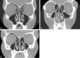

Concha bullosa

A concha bullosa is a pneumatized (air-filled) cavity within a nasal concha, also known as a turbinate. Bullosa refers to the air-filled cavity within the turbinate. [Source: Wikipedia ]